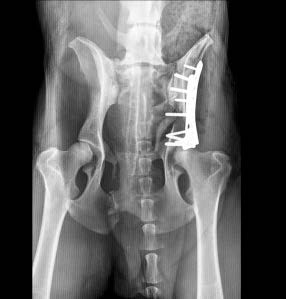

La clinique est équipée de matériel spécialisé

Ostéosynthèse par plaque standard, plaque verrouillée, fixateur externe